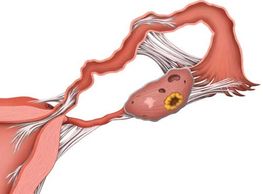

Endometriosis may produce scarring and blockage of the fallopian tubes

Scarring with adhesions may block the fallopian tube. Adhesions may result from prior surgery, infection, or endometriosis.

Normal pregnancy depends on a patent (open) fallopian tube for both transport of sperm up the fallopian tube near the ovary, and transport of the fertilized blastocyst down the tube toward the uterus.

A blocked fallopian tube can fill with fluid (hydrosalpinx), and then is predisposed to developing infection.

Blockage may be caused by endometriosis, prior infection, scarring, or unknown causes